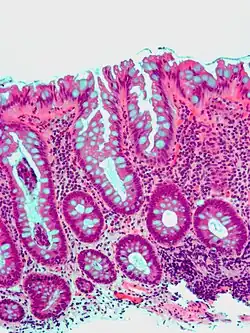

| Type | Risk of containing malignant cells | Histopathology | Image | |

| Villous adenoma | 15%[16] to 40%[15] | Over 75% villous[14] |

| |

The villous subdivision is associated with the highest malignant potential because they generally have the largest surface area. (This is because the villi are projections into the lumen and hence have a bigger surface area.) However, villous adenomas are no more likely than tubular or tubulovillous adenomas to become cancerous if their sizes are all the same.[18]

Micrograph of a villous adenoma. These polyps are considered to have a high risk of malignant transformation. H&E stain. -